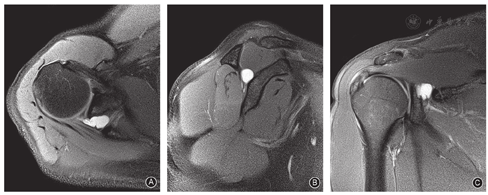

本研究共纳入11例,男7例,女4例;年龄29~56岁,平均(41.5±5.3)岁。体重指数15.60~32.73 kg/m2,平均(24.17±3.50)kg/m2。左侧3例,右侧8例。所有病例主要症状均为患侧肩后部疼痛不适。体格检查提示患侧冈下窝肌肉萎缩,肩关节后侧有固定压痛区,肩外旋肌力减弱。MRI均可见冈盂切迹处囊肿(图2),直径0.5~2.6 cm,平均(1.5±0.7)cm;其中3例合并上盂唇前后部(superior labrum anterior and posterior,SLAP)损伤,均为Snyder分型Ⅱ型。肌电图检查示肩胛上神经冈下肌支传导减慢,而冈上肌支传导正常。确诊依据肌电图检查结果。

经Wilmington入路置入关节镜,穿过冈上肌肌腹。监视下用射频将后上方关节囊沿盂唇外缘逐层切开,显露囊肿外壁(图3A)。用刨刀切开囊肿外壁,扩大囊肿外壁裂口,使囊液可以向关节内形成引流(图3B,图3C)。取部分囊肿壁做病理学检查。将关节镜慢慢通过囊壁裂口插入囊肿腔,适当刨除囊内分隔,直至显露肩胛上神经血管束。用刨刀、探钩小心分离神经血管束的筋膜,此处神经与肩胛上血管贴合紧密,镜下观察到血管搏动即可,不要求完全松解神经外膜(图3D)。切开的关节囊不做缝合。缝合切口,无菌纱布包扎,以三角巾固定肩关节并悬吊于胸前。